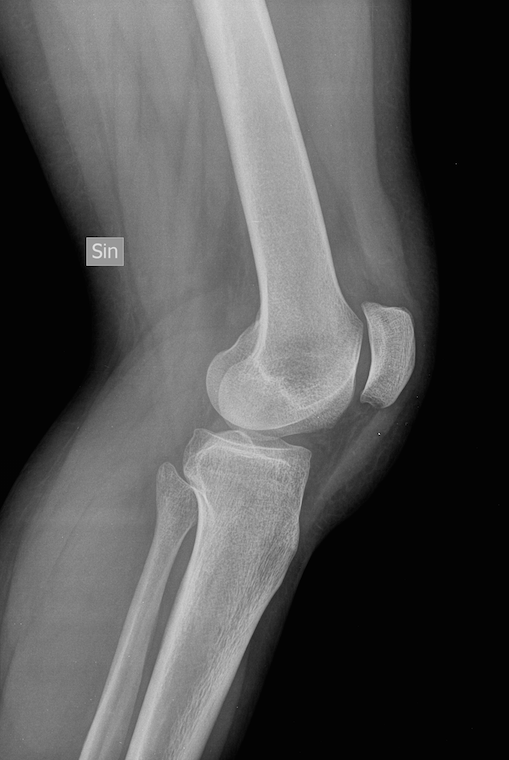

luxation patellar lussazione rotula.

rotula lussazione abituale rotulea bascula intervento esami radiografici.

rotula lussazione ginocchio articolazione rotulea normale tgvet paone imma posta dell.

rotula lussazione ginocchio gatto mediale.

lussazione rotulea associate scheletriche anomalie.

lussazione rotula eziologia patologia genetica sviluppa.

rotula cresta cane tibiale displasia trasposizione lussazione.

rotula lussazione cane lussata medialmente.